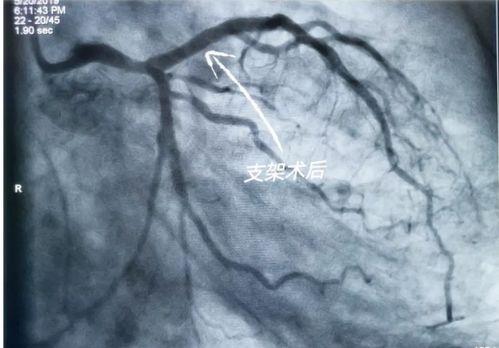

三、国产心脏支架的应用

国产心脏支架在我国的应用非常广泛。据统计,我国每年约有数十万例心脏支架手术,其中大部分采用了国产心脏支架。这些支架在临床应用中表现出良好的效果,为患者带来了福音。